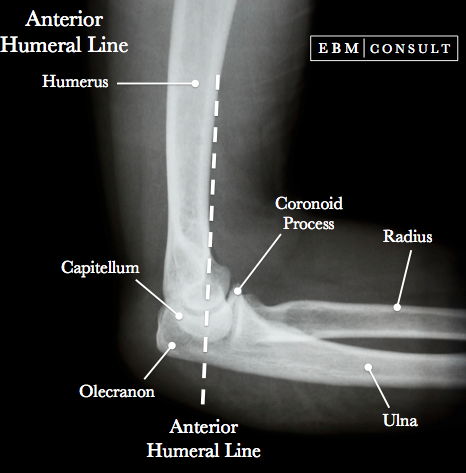

What is the anterior humeral line?

The anterior humeral line is a radiographic line that is drawn down the anterior margin of the humerus and through the middle third of the capitellum.

What is teh radiocapitellar line?

Line drawn along the longitudinal axis of the proximal radius. Normally the line passes through the capitellum. If it does not, there is radiocapitellar dislocation.